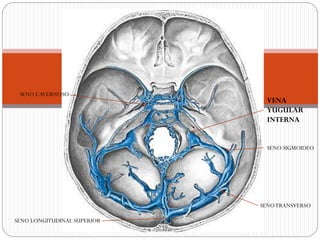

SENOTRANSVERSO

SENO SIGMOIDEO

SENO CAVERNOSO

VENA

YUGULAR

INTERNA

SENO LONGITUDINAL SUPERIOR